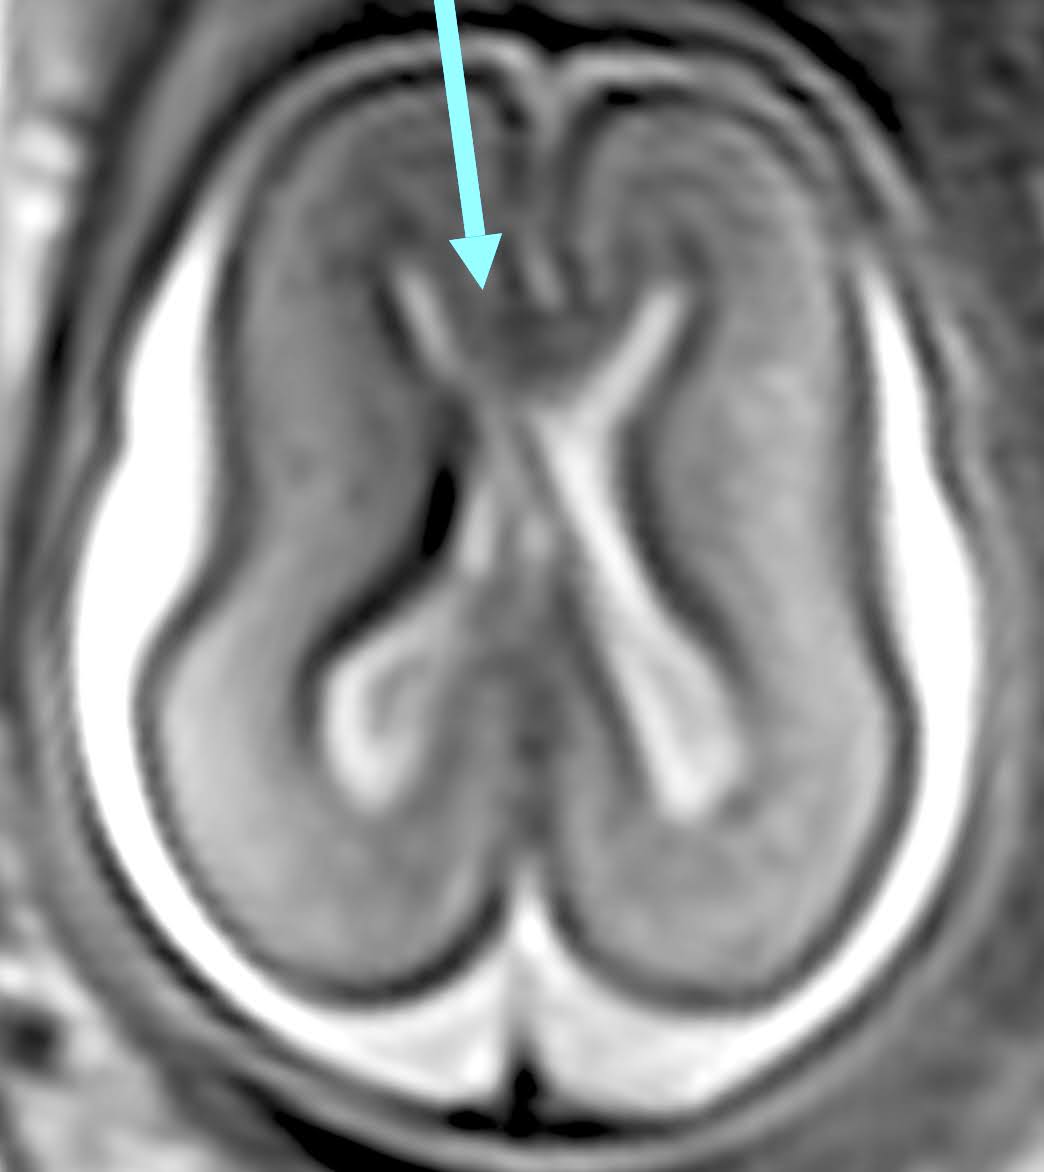

第一個個案妊娠23週時發現透明中膈腔型態有疑義,進一步檢查胼胝體,發現胼胝體形狀較短(圖一),進而安排胎兒磁振造影,影像上發現胼胝體的isthmus與splenium缺失(圖二),診斷為pACC。後續安排兩次超音波和一次fetal MRI,沒有發現其他結構異常,胎兒尚未出生,故會繼續追蹤出生後的狀況。一篇meta-analysis文獻比較完全性胼胝體發育不全(Complete agenesis of corpus callosum,)與部份性胼胝體發育不全的合併其他異常狀況及預後,發現pACC整體的預後都較差,最後文獻提出因為各項研究的個案數較少且缺乏一致性的神經發展評估系統,故期望能有更大型的研究出現。

![]() |

| 圖二、胼胝體較短(MRI) |